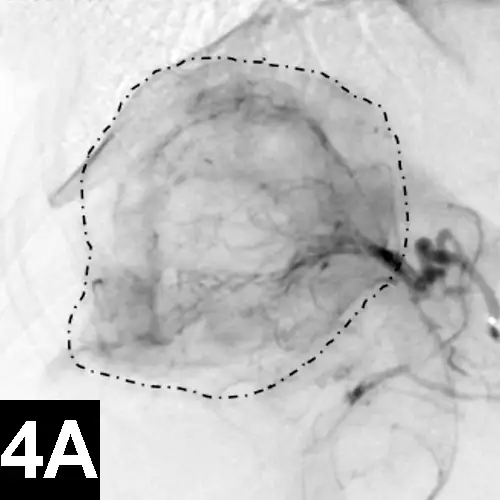

Figure 4A: Lateral digital subtraction angiograms of a dog with a nonresectable massive right-sided hepatocellular carcinoma.

The dog’s head is to the left.

Prechemoembolization angiogram demonstrating a massive liver tumor (surrounded by hyphenated line).